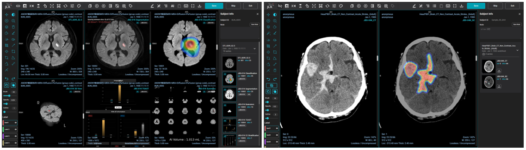

의료 인공지능 전문 기업 제이엘케이가 ‘뇌병변 정보 제공 장치 및 방법’에 대해 미국 특허에 등록했다. 해당 특허는 3차원의 자기공명 혈관영상 (MRA: Magnetic Resonance Angiography) 영상에서 정확하게 뇌병변 영역을 학습하고 분석할 수 있는 방법에 대한 원천 기술 특허다. 이를 통해 뇌혈관 영역에서 이상 병변을 검출할 수 있는 인공지능을 통해 뇌졸중 발병 리스크를 줄이고 추적 관찰할 수 있는 방법을 제공한다. 비급여 보험 수가를 획득한 제이엘케이는 전세계시장 진출을 위한 강력한 기술 장벽 기반을 마련하기 위하여 뇌종줄 분석과 발병의 원인을 찾을 수 있는 다양한 원천 기술 특허를 미국, 유럽, 일본, 중국 등 주요 선진국 시장에서 연이어 특허권을 취득했다. 특히 뇌졸중 환자를 치료하기 위한 진단 및 치료 과정에서는 CT, CTA, CTP, MRI, MRA 등 다양한 영상과 임상 정보들을 종합하여 판단하기 때문에 고려해야할 범위가 넓고 복잡성이 높다. 제이엘케이는 이러한 다양한 영상을 분석하여 종합하는 전주기 솔루션을 구축했다. 제이엘케이 김동민 대표는 “우리가 제시하는 뇌졸중 패러다임 전환 로드맵에 따른 미래 비전과 매출 목표를 이루기위해 미국 진출은 피할 수 없는 도전이고 과제이다.”라고 밝히며, “뇌졸중의 전주기 분석이라는 차별성을 기반으로 국내 시장에서 실증하고 기술 차별력과 방어력을 구축하여 미국과 일본 시장에서 본격적으로 매출 확장하는 시장 전략으로 글로벌 진출에 박차를 가하겠다”라고 밝혔다. 관련 기사 더보기 https://www.venturesquare.net/910227